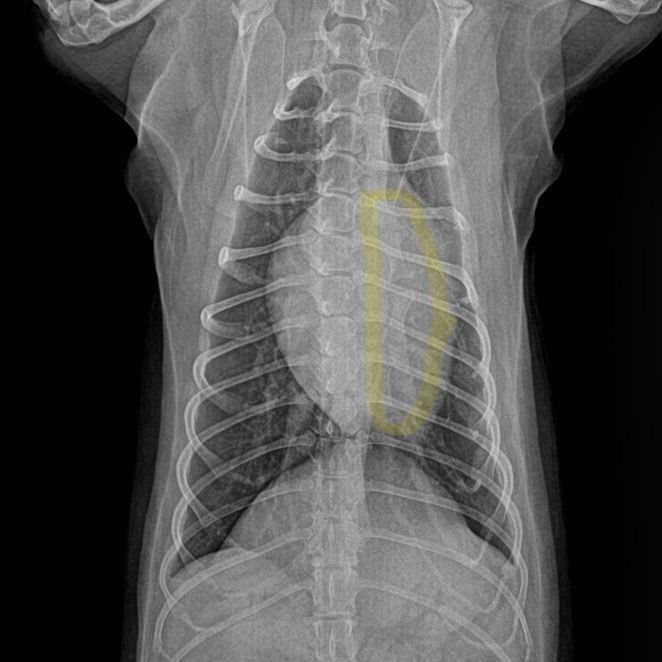

엑스레이는 흉골이 휜거같아 이상해서 세번정도 찍었다고 하네요. 사진 보면 노란색 표시 흉골이 휘어있고 심장도 쏠려있습니다…잘못찍었다고 흉골이 휘고 심장도 쏠릴 수 있나요?!?

첫번째 사진이 1년전 다른병원에서 찍은 엑스레이고 2,3번째가 이번에 찍은 흉골 휜 엑스레이입니다.. 3,4번째 흉골 휜 엑스레이 같은 사진인데 휜 흉골부분 노란색으로 표시해뒀습니다. R, L사진 둘 다 다른방향에서 찍은거같은데, 둘 다 휘어있습니다. 폐쪽의 문제일수도 있을까요? 기침이나 식욕감퇴 등의 다른 증상은 없고 변 상태도 좋습니다.